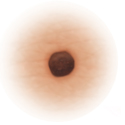

| Normal mole. |

Asymmetry

When half of the mole does not match the other half